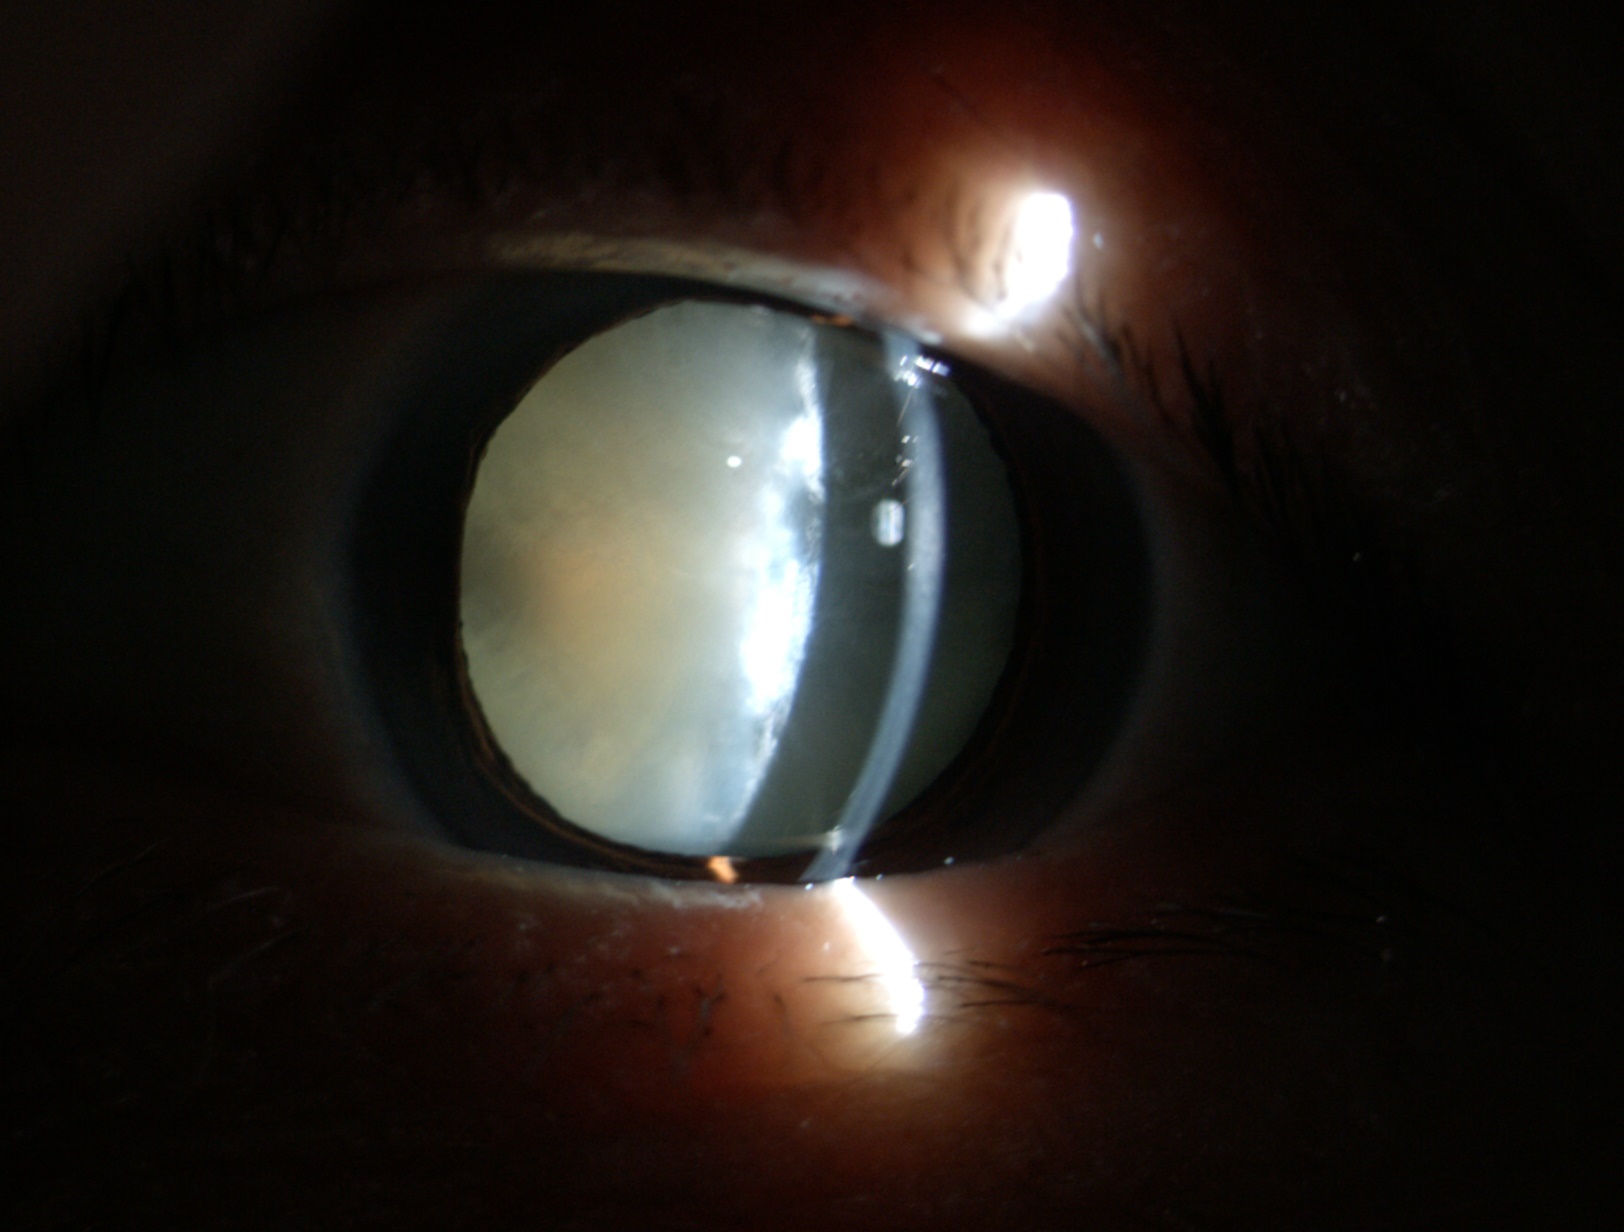

老年性白內(nèi)障

夏季強(qiáng)烈的陽光通常使瞳孔變小,此時往往視力下降更明顯,適合手術(shù)者更應(yīng)當(dāng)機(jī)立斷。